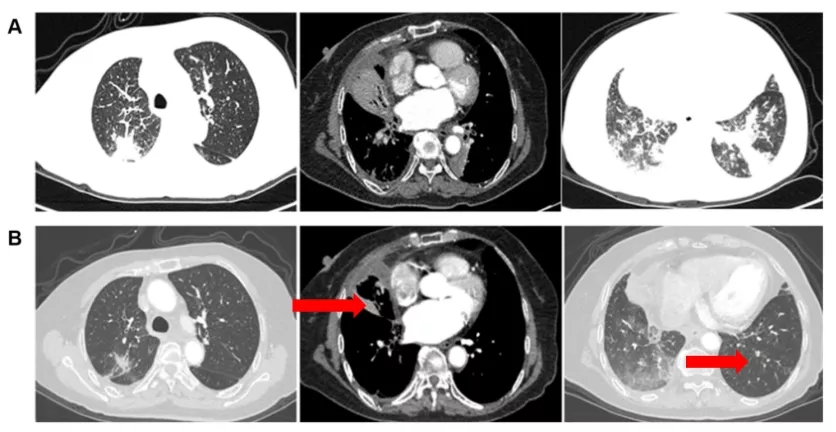

与上述多靶点抗血管生成药物相似,安洛替尼也主要通过抑制VEGFR1-3和成纤维细胞生长因子受体(FGFR)1-4。本文中三个临床案例均具有TP53突变,接受安罗替尼治疗后效果均为PR。基于这些以上数据,TP53突变患者可能是安罗替尼获益人群。当然更需要一个更大的临床前瞻性的随机对照试验来确认!小火苗,大希望!期待这一发现成为我们打开TP53突变肿瘤治疗的契机!